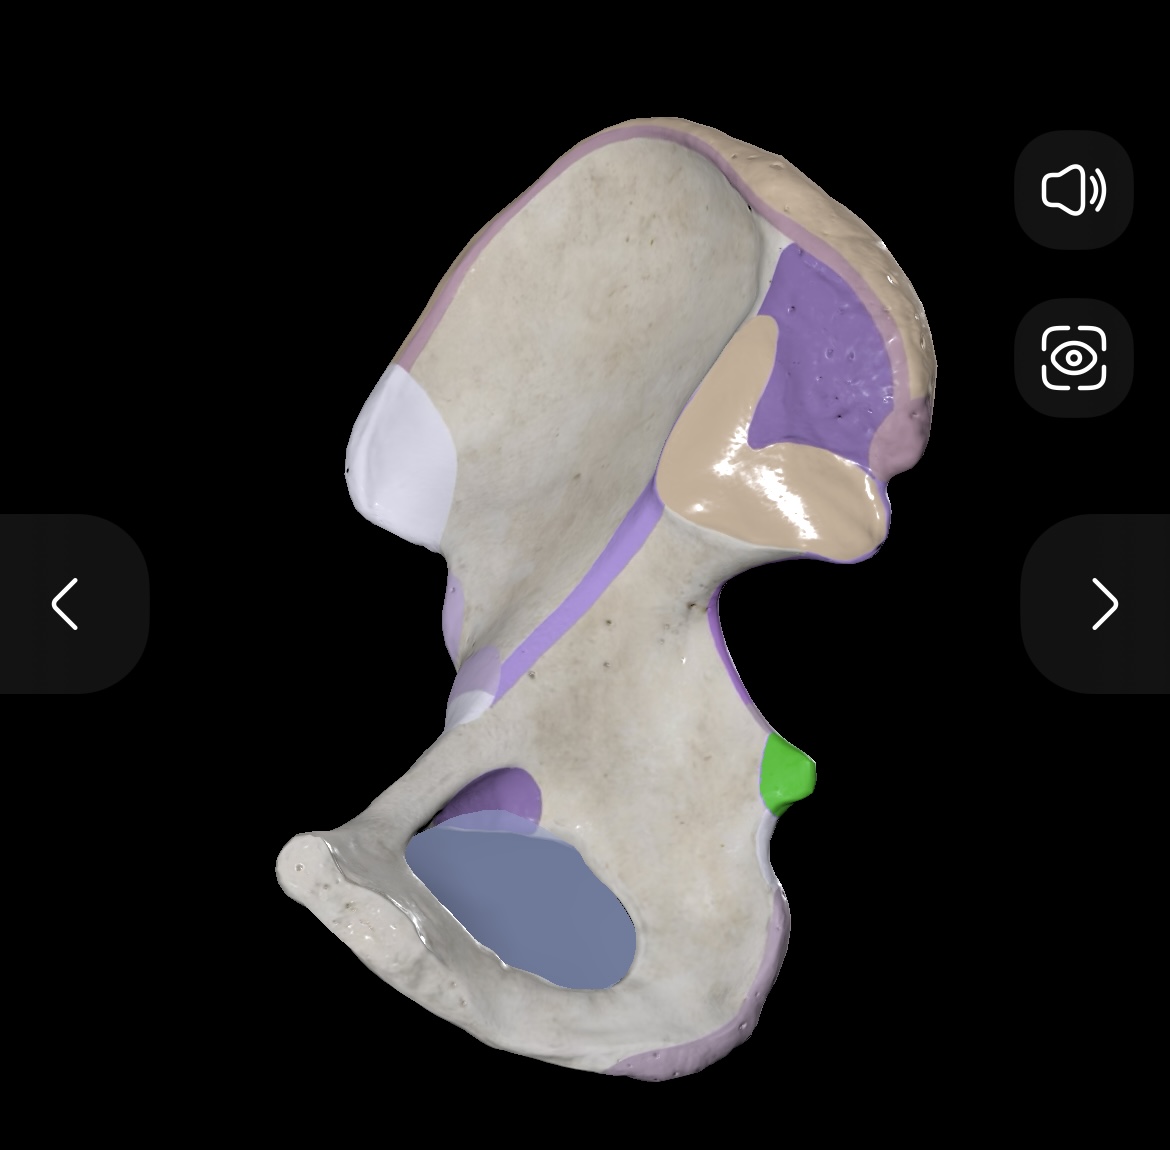

Illium

Ischium

Pubis

Ischial Spine of Ischium

Iliac Tuberosity of Illium

Anterior Superior Iliac Spine

Anterior Inferior Iliac Spine

Posterior Superior Iliac Spine

Posterior Inferior Iliac Spine

Iliac Crest

Acetabulum